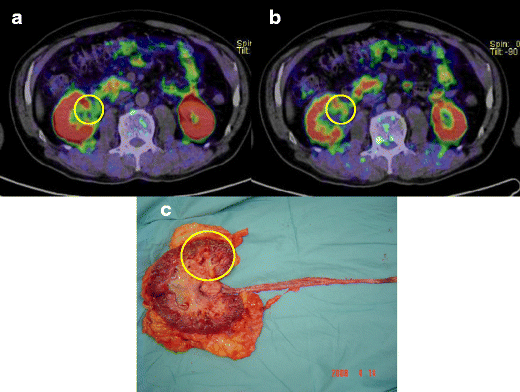

Urothelial carcinoma of the left renal pelvis in patient 1. a, b Choline PET/CT images of the primary tumour at 10 min (a) and 20 min (b) after injection. Choline uptake at 10 min is positive but weak (SUVmax 2.48) compared with that at 20 min (SUVmax 3.79). c Photograph of the primary tumour after resection. Circles tumour sites